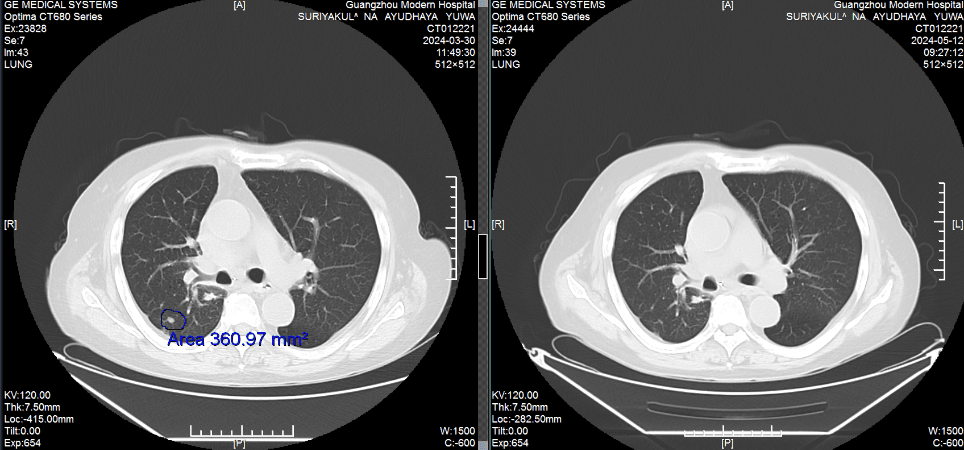

КТ-снимки подтвердили: опухоль в легком практически исчезла

Результаты: от отчаяния к теннису

• Через 2 курса лечения: Кашель и одышка уменьшились, метастазы в легких и печени значительно сократились. • Через 6 месяцев: Плевральный выпот исчез, вес вернулся к норме. • Июнь 2024: Мохамад отдыхал на Бали и играл в теннис.